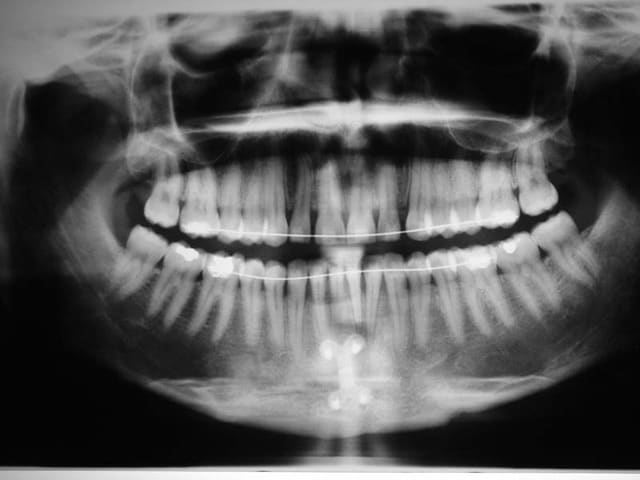

On voit bien le changement de profil sur les radios .

la génioplastie n’a pas été une réussite la 1° fois, toutes les Rx. sont avec le résultat de cette génioplastie

pour ceux qui ne se rappellent pas bien de l’analyse esthétique de Ricketts, voici qq. tracés

"""Tu as placé du compo sur le post du bas, ouvrant la DV post, ce qui change le profil, non ?"""

oui, en cours de TTT.

la derniere Rx. et les photos de visage sont prises avant qu'elle retourne voir son 2° chirurgien et sont sans compo